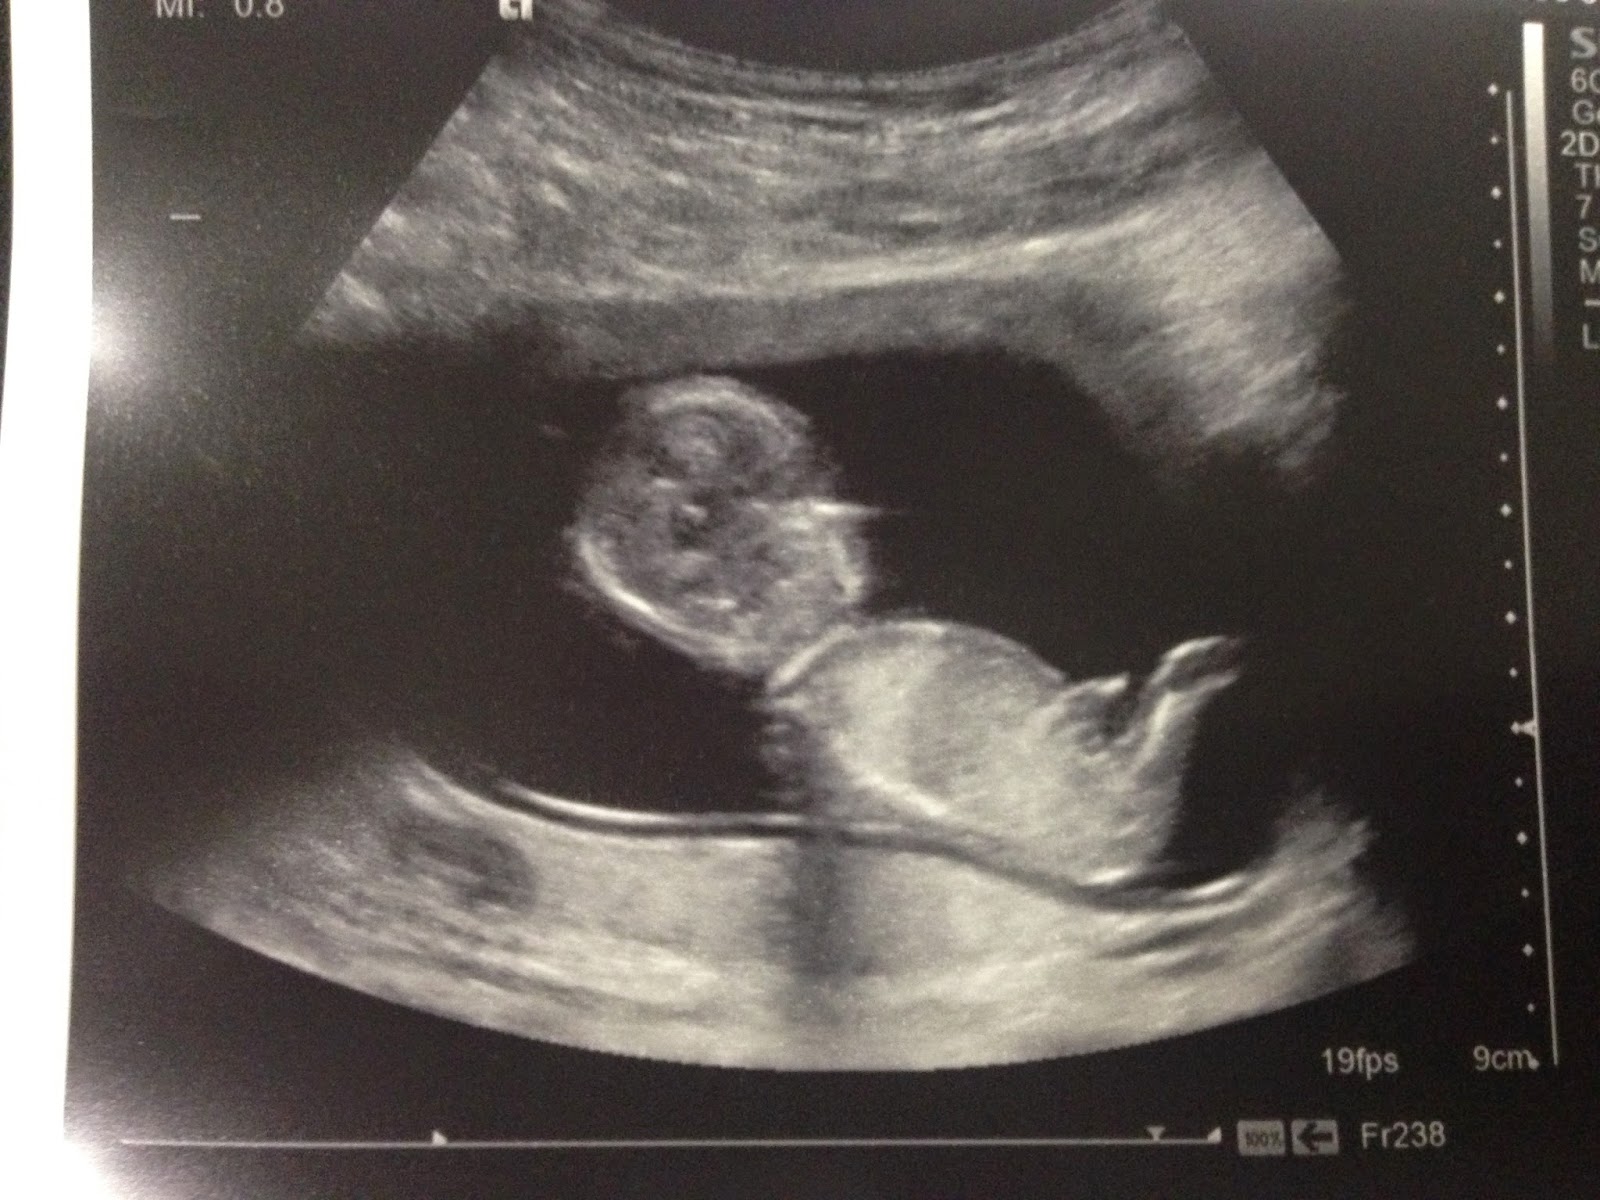

Dating Scan 13 Weeks

From this week onwards, your baby will grow rapidly and your doctor might suggest an ultrasound scan to check his progress . An ultrasound scan in the 13 th week can tell you a lot about your baby's health and is important . So read on to know why you should have an ultrasound scan at 13 weeks and how it is performed .

If you're pregnant in England you'll be offered an ultrasound scan at around 10 to 14 weeks of pregnancy . This is called the dating scan . It's used to see how far along in your pregnancy you are and check your baby's development . The scan may also be part of a screening test for Down's syndrome . Your midwife or doctor will book you a dating scan appointment . It will usually take place at your local hospital ultrasound department .